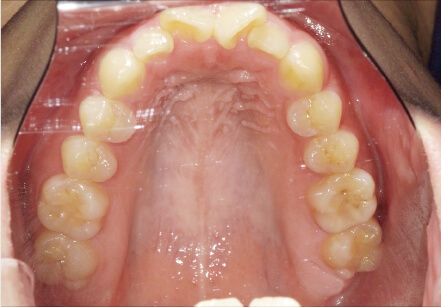

叢生の症例

19歳

女性

相談内容

上の前歯が出っ歯、下の前歯がガタガタ

カウンセリング・診断結果

抜歯承諾、IPR承諾、アタッチメント承諾、ミニインプラント承諾、アレルギー有・叢生(凸凹)

治療内容・方法

全顎アライナー矯正 抜歯予定だったが抜歯リスク高いため抜歯なしでIPR量を増やす

術後の経過・現在の様子

クリアライナー

治療のリスク

痛み・歯根吸収・歯肉退縮・虫歯・後戻り

費用・治療期間

880,000円、1年5ヶ月